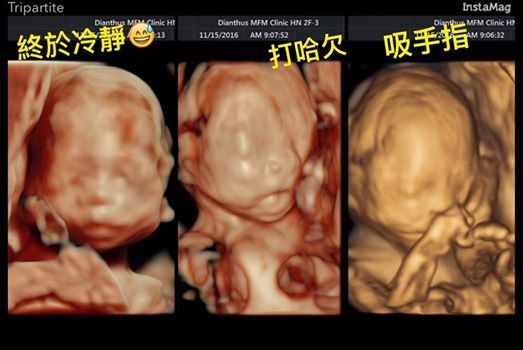

幸好滾了一晚的她都早上檢查的時候終於恢復冷靜

而且姿勢很配合,順利地從頭、眼、鼻、唇、四肢、手指腳趾、心肝脾肺腎胃膽都看得一清二楚

這張有蛋包的眼睛,雖然我是她媽還是要說:你不要這樣看我我好害怕XDDD

腿一直在踢我的肚子!一直踢!!!

醫生也會趁胎兒臉比較清楚的時候拍幾張3D超音波讓爸媽過過乾癮